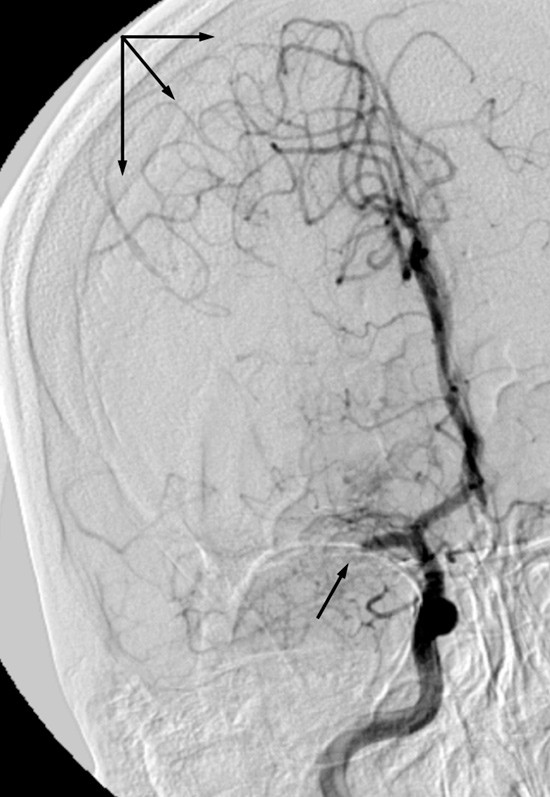

En kvinne tidlig i 30-årene ble innlagt i sykehus med akutte pareser i venstre kroppshalvdel. CT-angiografi viste okklusjon av høyre a. cerebri medias hovedstamme, og det ble startet intravenøs trombolytisk behandling. Under pågående infusjon ble hun sendt til Oslo universitetssykehus for endovaskulær behandling. Det ble utført vellykket embolektomi, med rekanalisering av arterien og rask klinisk bedring. Angiogrammene viser venstre fremre kretsløp før (venstre) og etter (høyre) prosedyren. National Institutes of Health Stroke Scale (NIHSS) ble skåret til 11 poeng ved innkomst (moderat alvorlig hjerneslag), 4 etter prosedyren (milde slagsymptomer) og 1 ved utskrivning (nær symptomfri). Av kjente vaskulære risikofaktorer bemerket vi røyking og bruk av p-piller.